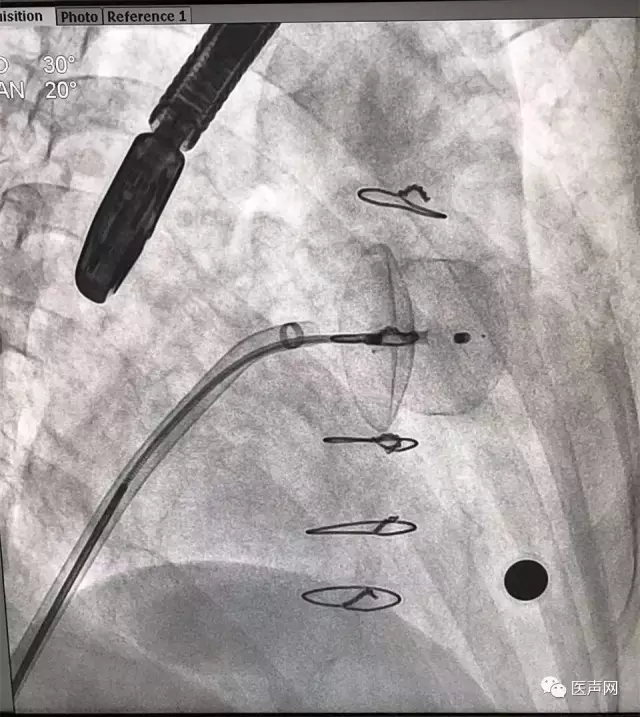

ACP放置

ACP成功释放

左心耳造影